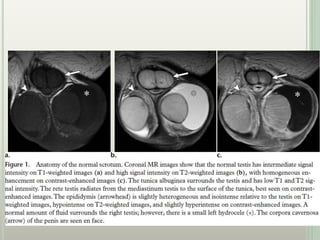

 The normal testis is a sharply demarcated homogeneous oval

structure with low to intermediate signal intensity on T1WI

and high signal intensity on T2WI .

 The testis is surrounded by the tunica albuginea, which has

low T1 and T2 signal intensity.

 The mediastinum testis has signal intensity similar to that of

the testis on T1WI and is lower in signal intensity than the

testis on T2WI.

 The rete testis radiates from the mediastinum testis to the

surface of the tunica.

 High signal intensity of the testis on T2-weighted images

allows excellent depiction of focal solid testicular masses,

which most commonly have lower T2 signal intensity.

 T1WI are useful in detection of fat or methemoglobin,

both of which have high signal intensity.

 The epididymis is slightly heterogeneous and isointense

to the testis on T1-weighted images.

 The epididymis is more clearly differentiated from the

testis on T2-weighted images because it has lower signal

intensity than the adjacent testis.

 Contrast material–enhanced images demonstrate

homogeneous enhancement of the testis and

hyperintensity of the epididymis relative to the testis.